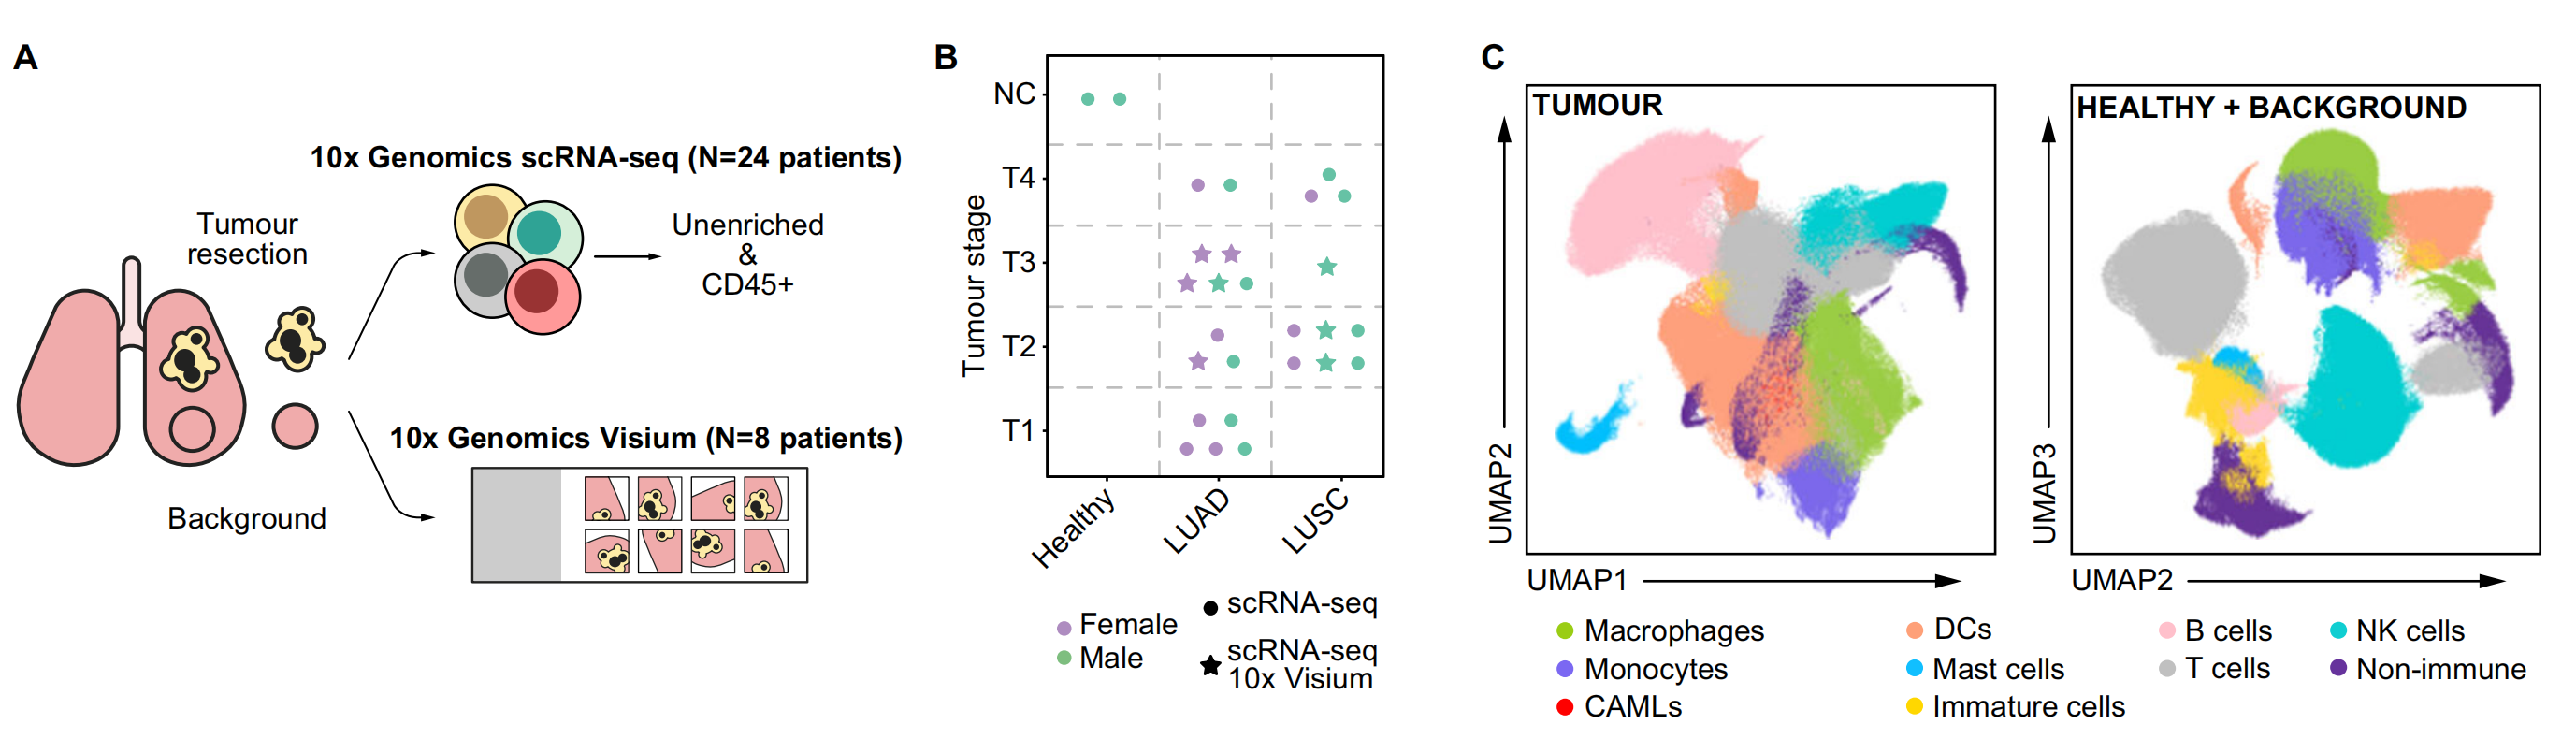

这篇文章是一项关于非小细胞肺癌(non-small cell lung cancer, NSCLC)的单细胞和空间转录组学分析研究。

研究团队由Marco De Zuani、Haoliang Xue、Jun Sung Park等人组成,他们从25位未接受治疗的肺腺癌和鳞状细胞癌患者中收集了大约90万个细胞进行分析。研究发现肿瘤生态系统中存在多种免疫细胞类型,尤其是髓系细胞,在疾病进展中扮演重要角色。

研究结果揭示了抗炎性巨噬细胞与NK细胞/T细胞之间的负相关关系,以及肿瘤内NK细胞的细胞毒性降低。尽管肺腺癌和鳞状细胞癌在细胞类型组成上相似,但在多种免疫检查点抑制剂的共表达上存在显著差异。此外,研究还发现了肿瘤中巨噬细胞的转录“重编程”,使它们趋向胆固醇输出,并采取类似胎儿的转录特征,这有助于铁的外排。

这项多组学资源提供了肿瘤相关巨噬细胞的高分辨率分子图谱,增进了我们对其在肿瘤微环境中角色的理解。研究还发现肿瘤与邻近肺组织相比,具有更高多样性的免疫和非免疫细胞。在肿瘤中,成纤维细胞和淋巴内皮细胞的比例发生了变化,并且上皮细胞的多样性增加。

研究还探讨了肿瘤微环境中的细胞间相互作用网络,发现肺腺癌和鳞状细胞癌虽然在细胞组成上相似,但在细胞间相互作用网络上存在差异。例如,某些免疫检查点抑制剂及其相应的抑制分子在两种癌症中的共表达不同。研究还发现,在肿瘤微环境中,巨噬细胞亚群之间存在连续性,并且STAB1+巨噬细胞可能与肿瘤细胞紧密相关。

此外,研究还发现肿瘤巨噬细胞在肿瘤微环境中经历了“重编程”,采取了有利于胆固醇外排和铁外运的转录特征,从而支持肿瘤的进展。研究结果为开发针对NSCLC的更有效治疗策略提供了重要信息。

Fig. 1 展示了非小细胞肺癌(NSCLC)异质性的单细胞转录组学分析结果。

以下是对图中各个部分的分析:

A. 研究概述:从切除的肿瘤组织、邻近未受累组织(背景)以及已故捐赠者的健康肺中制备了单细胞悬浮液,并富集了CD45+或CD235-的细胞进行单细胞RNA测序(scRNA-seq)。使用新鲜冷冻的肿瘤、背景和健康组织的冷冻切片进行10x Genomics Visium空间转录组学研究。

B. 队列概览:符号代表了个体患者以及执行的分析。

C. UMAP投影:展示了肿瘤和结合背景+健康数据集的UMAP(Uniform Manifold Approximation and Projection)投影图,这是一种用于降维和数据可视化的技术。

D. 点图(Dotplot):显示了用于肿瘤样本中宽泛细胞类型注释的代表性基因。点图通常用于展示基因表达水平,点的大小代表表达量,颜色代表表达水平的变化。

E. 等高线图(Contour plot):展示了在AT2细胞(44,399个细胞)、CAMLs(2520个细胞)和AIMφ(16,120个细胞)中共表达的髓系(LYZ, CD68, MRC1)和上皮系(EPCAM)基因。这些数据被标准化、缩放和对数转换。

F. 箱线图(Boxplot):展示了在AT2细胞、CAMLs和AIMφ中髓系(LYZ, APOE, CD68, MRC1)和上皮系(EPCAM, KRT8, KRT19)基因的标准化、缩放和对数转换后的基因表达。箱形图显示了四分位数,须表示1.5倍四分位距。

G. 非免疫细胞亚群的相对比例:在CD235-富集中计算的肿瘤与背景之间的差异。箭头指示了肿瘤与背景相比的增加(↑)或减少(↓)。使用双边Wilcoxon秩和检验和Bonferroni校正进行多重比较。**P < 0.01。没有星号的箭头表示该细胞类型仅在肿瘤或背景中发现。

H. 广泛免疫细胞的相对比例:在所有免疫细胞中识别的CD235-富集中计算的肿瘤与背景之间的差异。箭头指示了肿瘤与背景相比的增加(↑)或减少(↓)。使用双边Wilcoxon秩和检验和Bonferroni校正进行多重比较。*P < 0.05, **P < 0.01, ***P < 0.001。没有星号的箭头表示该细胞类型仅在肿瘤或背景中发现。

I. 肿瘤和背景中NK、DC、B、T细胞和巨噬细胞亚群的相对比例:在CD235-富集中计算的广泛注释内的肿瘤与背景之间的差异。箭头指示了肿瘤与背景相比的增加(↑)或减少(↓)。使用双边Wilcoxon秩和检验和Bonferroni校正进行多重比较。***P < 0.001。没有星号的箭头表示该细胞类型仅在肿瘤或背景中发现。

总体而言,Fig. 1 通过单细胞转录组学和空间转录组学技术,揭示了肿瘤组织与邻近正常组织在不同细胞类型上的异质性和差异。这些结果有助于深入理解肿瘤微环境中细胞的复杂性,并为未来的治疗策略提供潜在的靶点。